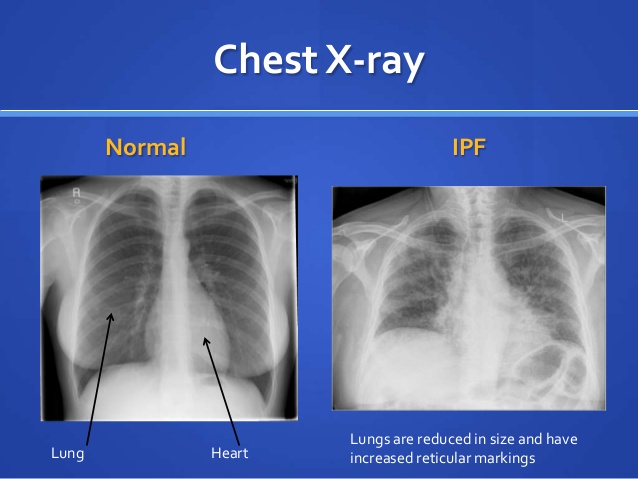

_正常肺部與肺纖維化X線對比

_特發性肺纖維化症狀

_特發性肺間質纖維化

A:特發性肺纖維化是一種慢性的進行性的纖維化性間質性肺炎,組織學和胸部螺旋CT特徵性表現為普通型間質性肺炎,病因不清,好發於老年人。特發性肺間質纖維化包括特發性肺纖維化的診斷標準,以及特發性肺間質纖維化急性加重期的診斷標準,特發性肺間質纖維化診……